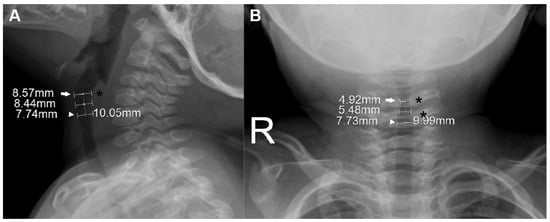

2.2. Definitions of Laryngeal Levels

2.3. Measurement of Laryngeal Dimensions